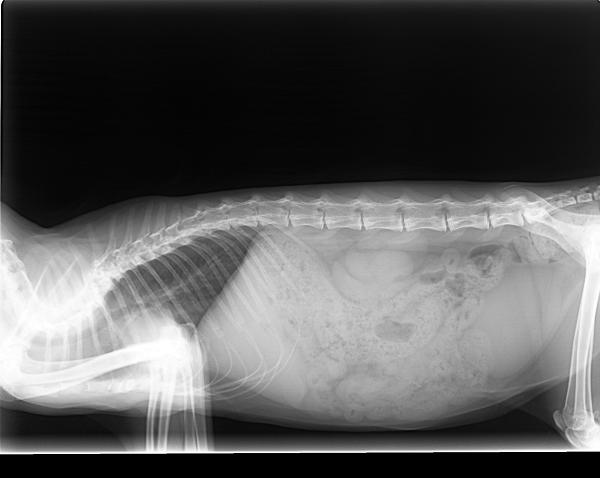

La columna vertebral es una parte del esqueleto de los gatos que está constituida por vértebras y se prolonga desde el cuello hasta la cola. Es la estructura clave que soporta el cuerpo de los gatos. En otras palabras, es la base de la estabilidad del organismo felino.

Los gatos presentan 7 vértebras cervicales, 13 vértebras torácicas, 7 vértebras lumbares, 3 vértebras sacras y unas 22 vértebras caudales.

Juntas forman una columna vertebral hiperflexible, más que la de cualquier otro animal, con discos intervertebrales muy suaves y también flexibles. Además, sus escápulas no están unidas a los miembros torácicos, sino que se encuentran libres, lo que les ofrece más agilidad y la capacidad de saltar y de hacer movimientos más complicados.